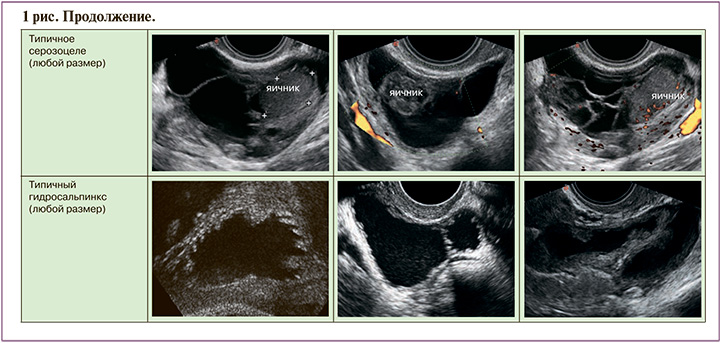

ORADS 2 – однозначно доброкачественная категория (риск злокачественности 1%); в нее вошло большинство однокамерных кист менее 10 см: простые кисты; несложные однокамерные с гладкими внутренними стенками и кисты, которые могут быть описаны с помощью классических доброкачественных поражений и их дескрипторов, если их максимальный диаметр составляет менее 10 см. К ним относятся: типичная геморрагическая киста, дермоидная киста, эндометриома, параовариальная киста, серозоцеле и гидросальпинкс (рис. 1). Хотя анализ васкуляризации не включен в оценку поражений в категории ORADS 2, он проводится в обязательном порядке, особенно при наличии геморрагических кист с ретрактированным сгустком, чтобы исключить солидный васкуляризированный компонент.